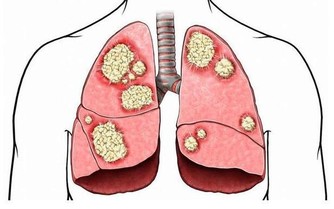

腎臟是我們人體中一個很重要的器官,雖然每個人都有兩個腎臟,但是哪怕有一個出現了問題,那麼也會影響整個腎功能。所以,我們需要時刻關注自己的腎臟健康,以防發生慢性腎功能衰竭。

慢性腎功能衰竭,簡稱慢性腎衰,是大家經常說的“尿毒症”,屬於人類十大死因之一。我國慢性腎衰患者中,80%以上的患者發病誘因是高血壓、糖尿病和慢性腎炎。